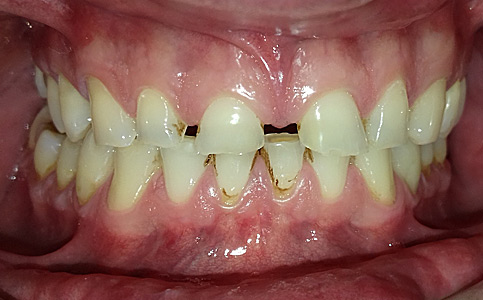

Pacjent zgłosił się z powodu niezadowalającego koloru i kształtu zębów, nie chciał także szlifować swoich zębów pod licówki/korony. Odpowiedzią na jego potrzeby był BONDING czyli estetyczna odbudowa kompozytowa. Przed wykonaniem BONDINGU pacjent był zdeprogramowany aby ustawić staw skroniowo-żuchwowy w dobrej i wygodnej pozycji, zostały odbudowane zęby tylne do kształtów anatomicznych oraz podniesienie w zgryzie aby móc estetycznie przedłużyć zęby przednie. Efekt leczenia sprawił że Pacjent opuścił nasze Centrum stomatologii i Ortodoncji z szerokim uśmiechem.